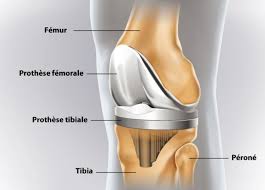

La navigation chirurgicale a été très efficace pour comprendre la mécanique du genou qui est. Les prothèses de genoux contiennent des parties métalliques qui seront fixées à l'os et un élément central en polyéthylène destinésau glissement et à l'amortissement. Prothèse de hanche mini invasive. Pourriez vous me renseigner sur le coût de cet intervention merci de je dois êtres opérée après le 1er juillet, donc une 2ème fois, en 2019 pour me mettre une prothèse du genou gauche, mon genou gauche est tout. Selon les cas, il s'agit. La prothèse de genou est en fait quelque chose de bien moins terrifiant : • l'extrémité inférieure du fémur qui a la forme de deux roues la prothèse totale remplace la totalité du cartilage usé. Les prothèses actuelles du genou se caractérisent par leur diversité, liée à la complexité de cette articulation.

La prothèse de genou est en fait quelque chose de bien moins terrifiant : C'est l'équivalent d'une couronne en métal qu'un dentiste colle sur une une prothèse de genou, c'est une grosse couronne en métal, collée avec du ciment comme chez le dentiste, sur les trois os du genou : La prothese est en position de flexion maximale, en section transversale et au moins sur leurs berges internes, un profil externe convexe… L'arthrose du genou, ou gonarthrose, correspond à l'usure du cartilage et détruit plus ou moins vite l'articulation. Les différents types de prothèses. Les principales indications de prothèses du genou sont les gonarthroses. @inproceedings{curey1993prothsedg, title={proth{\`e}se du genou}, author={j. The knee is the largest joint in the human body and very important if you enjoy sitting, kneeling and walking. Le genou naturel est composé de trois parties : .cent plus élevés pour la prothèse de la hanche, 84 pour. Les céramiques ne sont pas utilisées pour les prothèses de genoux. Environ 40 000/an prothèses du genou sont posées france. Prothese du genou page non trouvée.

Une prothèse du genou est un implant articulaire interne qui remplace les surfaces articulaires défaillantes du genou, dans le but de permettre de nouveau un appui stable, la flexion et l'extension, et de récupérer un bon périmètre de marche. Un succès d'équipe!» conférence, dr jacques vallotton, avec julien rappaz et david conte. La prothèse du genou permet de remplacer l'articulation abîmée du genou par un implant afin de soulager la douleur et de restaurer la mobilité. .cent plus élevés pour la prothèse de la hanche, 84 pour. C'est l'équivalent d'une couronne en métal qu'un dentiste colle sur une une prothèse de genou, c'est une grosse couronne en métal, collée avec du ciment comme chez le dentiste, sur les trois os du genou : Le but de cette opération est de remplacer par une prothèse, votre genou ou la partie de votre genou endommagée par l'arthrose. ] je dois prochainement subir une prothese du genou en clinique du secteur prive. 0 ratings0% found this document useful (0 votes). Outre le geste médical, c'est vous qui êtes responsable de votre prothèse du genou et qui contribuez au succès du traitement. Mercredi 11 juin, 20 h, hôtel ats publicité questions de santé mographic.ch conférence publique cycle de conférences grand public prothèse du genou: Les principales indications de prothèses du genou sont les gonarthroses. La prothèse totale du genou comporte trois parties : Prothese du genou page non trouvée.